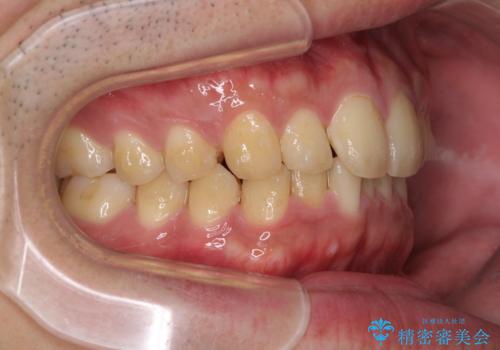

- 上下前歯のデコボコと下の前歯が隠れるほどの深い咬み合わせを気にして来院された患者様です。

インビザラインによる上下歯列の拡大と、IPR(歯と歯の間を削る)にるスペースの獲得により、口元のデコボコとディープバイトを改善することとしました。

デコボコがなくなったことで日頃の清掃が行いやすくなり、深い咬み合わせが改善したことで、食いしばりによる顎の負担も軽減されました。